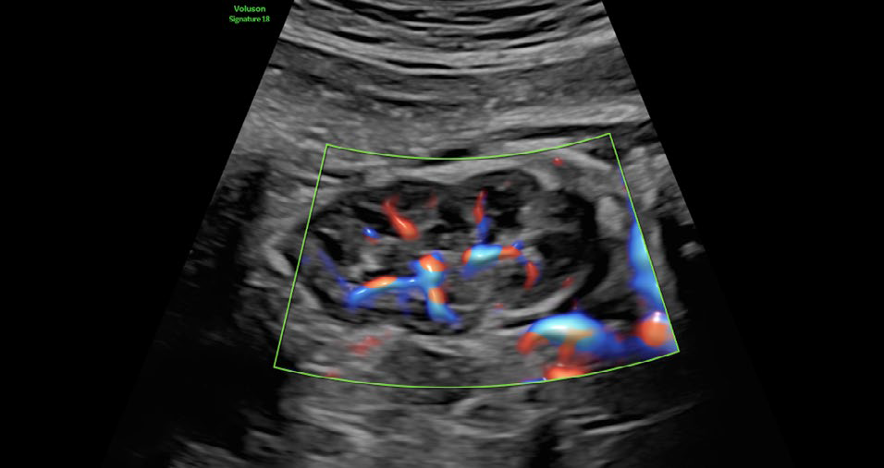

• RadiantflowTM

Calidad de color mejorada y mayor sensibilidad

Separación mejorada entre vasos sanguíneos que proporciona la percepción de un flujo sanguíneo dinámico, añade información de altura y profundidad para una apariencia 3D, Menos destellos, límites vasculares mejorados e Identificación fácil y rápida incluso de los vasos más pequeños.